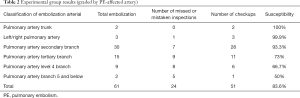

This computer-aided diagnostic system was applied to 40 cases in the experimental group. The results are shown in Table 2. The detection rate of branches at all levels obtained by this method was similar to that of the test group, and the FP rate was also increased as the arterial classification became finer. The number of errors increased significantly, sensitivity reduced, and detection sensitivity was positively correlated with arterial classification.

Full table